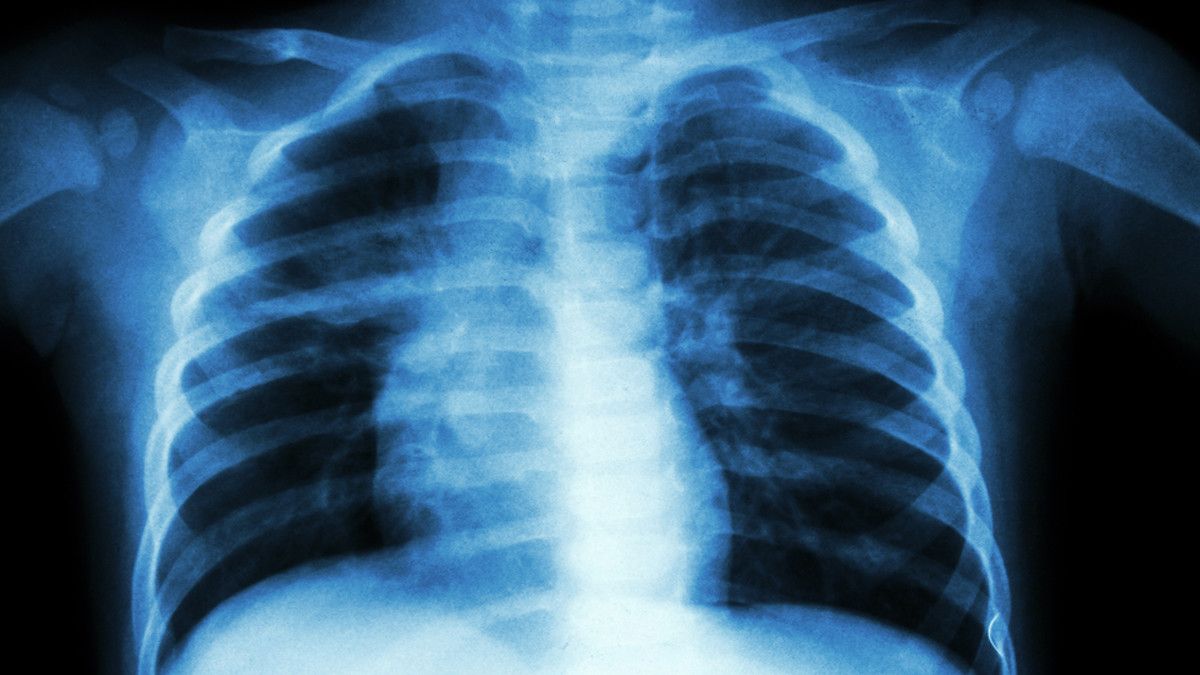

Komplikasi Pneumonia pada Anak

Pneumonia termasuk penyakit berbahaya yang bisa mengancam nyawa. Berikut ini adalah beberapa komplikasi pneumonia pada anak yang mesti diwaspadai:

Gagal Napas

Jika pneumonia sudah masuk dalam tahap berat, risiko terjadinya gagal napas akan meningkat berkali-kali lipat. Jika kondisi ini tidak segera mendapatkan penanganan tepat dari pihak medis, risiko terjadinya kekurangan oksigen yang berujung kematian mungkin tak bisa dihindari lagi.

Bakteremia

“Ketika pneumonia sudah memburuk, infeksi akan meluas ke aliran darah. Akibatnya, proses penyembuhan lebih sulit untuk dilakukan,” ujar dr. Devia.

“Kondisi ini juga bisa menyebabkan kegagalan pada fungsi organ selain paru-paru, syok septik, dan kemudian meninggal dunia,” lanjutnya.

Efusi Pleura

Infeksi di paru bisa menyebabkan penumpukan cairan di selaput pleura, yaitu selaput tipis yang melapisi bagian luar paru-paru dan bagian di dalam tulang rusuk

Semakin banyak cairan yang ada di paru-paru, semakin sesak pula laju pernapasan pasien. Lama-kelamaan, kondisi ini bisa menyebabkan tubuh kekurangan oksigen dan berujung pada hilangnya nyawa pasien.